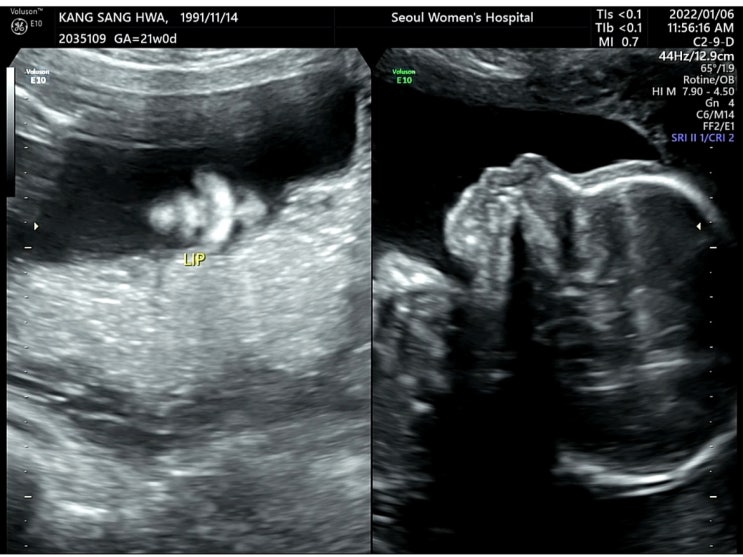

[찰떡일기??] 임신21주: 인천서울여성병원에서 2차정밀초음파 검사한 후기/2차정밀초음파 시기/2차정밀초음파 소요시간/용어 정리

연락처: 032-247-2000 주소: 인천광역시 미추홀구 경원대로 771 홈페이지: https://incheon.smch.co.kr/ind...